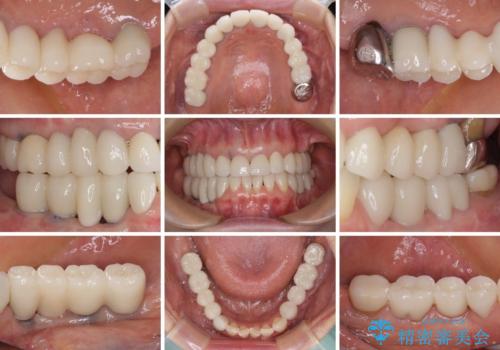

- 以前治療した歯が欠けたり、痛みを感じたりしているとのことで来院された患者様です。

アメリカ国内を転々としながら治療を行ったため治療跡がモザイク様で、クラウンが壊れていたり、抜歯が必要であったりしていました。

上下左右すべての奥歯に処置が必要であり、同時に行うと食事が取りにくくなってしまったり、手前の歯に負担がかかって初診時よりも状況が悪化したりする可能性があるため、片方ずつ処置を進めて行くこととしました。

下顎右側は骨造成を併用してインプラント治療を行い、その他の奥歯もインプラントや歯周外科処置を併用して補綴治療を進め、最後に前歯部の欠けてしまったセラミッククラウンを作り替えることとしました。

海外を拠点に仕事をされているため、日本国内への入国規制の時期が重なってしまい、予定していたよりも1年ほど長い治療期間がかかってしまいました。